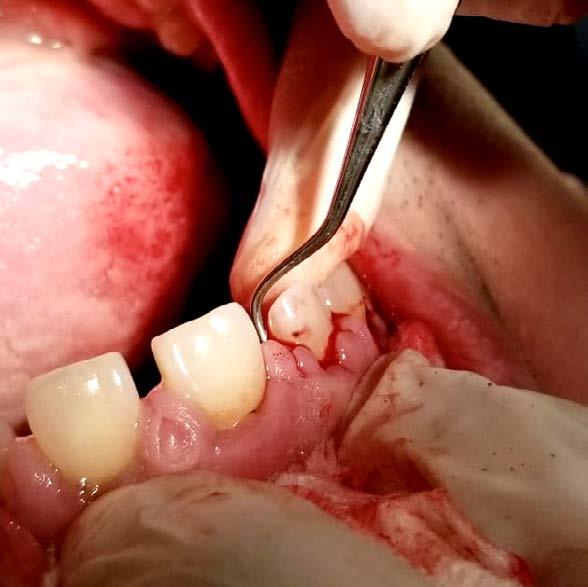

Figura 3. Protocolo de fresado quirúrgico: a) fresa piloto sentido horario, b) comprobación radiográfica, c) RX pin de paralelismo, d) fresa 2.3 sentido antihorario, e) comprobación radiografía periapical de posición y elevación del piso de seno, f) fresa 3.2 a 9mm con elevación evidente, g) verificación de profundidad con sonda del kit de implantes, h) colocación de injerto de hueso NovaBone, i) vista del hueso en el lecho quirúrgico j) fresa final diámetro 4.3, k) RX de comprobación de fresa 4.3 y l) RX de implante e injerto colocados.

Se llevó a cabo una técnica anestésica infiltrativa supraperióstica en el fondo del vestíbulo. Se realizó una incisión sulcular contorneante en los dientes adyacentes (15 y 17) sin necesidad de incisiones liberatrices.

El protocolo de oseodensificación se ejecutó siguiendo una secuencia de fresado en sentido antihorario, salvo por la fresa piloto inicial, que operó en sentido horario a 1200 rpm, bajo abundante irrigación con solución fisiológica. Se inició el procedimiento con una fresa Versah de 2.5 mm de diámetro, hasta alcanzar una profundidad de 5 mm, seguida por una fresa de 3.0 mm hasta los 8 mm de profundidad. Posteriormente, se empleó una fresa de 3.2 mm hasta los 9 mm de profundidad para elevar la membrana sinusal en esta fase del protocolo.

En este punto, se aplicaron 5 cc de biomaterial sintético NovaBone en jeringa directamente en el lecho quirúrgico y se proyectaron mediante

fresado (fresa de 4.2 mm de diámetro) dentro del sitio preparado como indica el protocolo de fresado Versah. Gracias al diseño específico de las fresas, el biomaterial fue distribuido hacia las zonas superior y lateral del sitio quirúrgico para promover una adecuada condensación ósea y facilitar la colocación del implante en una posición subcrestal de 1 mm.

Entre cada cambio de fresa, se verificó radiográficamente la dirección y profundidad del fresado. Finalmente, se completó el protocolo con el uso de la fresa de 4.2 mm de diámetro hasta alcanzar una profundidad final de 9 mm. Se obtuvieron imágenes radiográficas que evidencian la correcta colocación del injerto en la elevación lograda (ver Figura 3).